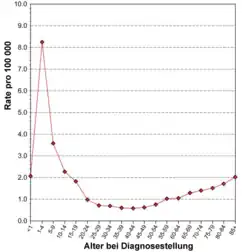

Die ALL ist eine seltene Erkrankung mit einer Inzidenz von etwa 1,5 Neuerkrankungen/100.000 im Jahr bezogen auf alle Altersgruppen. Es besteht ein Übergewicht von männlichen Erkrankten (1,4 zu 1). Für Deutschland schätzt man etwa 500 Neuerkrankungen bei Erwachsenen und ca. 500 Neuerkrankungen bei Kindern pro Jahr. Genaue Zahlen existieren für Erwachsene wegen des Fehlens eines zentralen Krebsregisters nicht, die Zahlen für Kinder unter 15 Jahren beruhen auf den Daten des Deutschen Kinderkrebsregisters, in dem schätzungsweise 90 % aller Fälle erfasst sind.[2] In der Schweiz und in Österreich werden jeweils etwa 40–50 Neuerkrankungen bei Erwachsenen und Kindern pro Jahr angenommen.[3] Für die Vereinigten Staaten werden die Neuerkrankungen im Jahr 2007 auf ungefähr 5200 Fälle geschätzt.[1] Das lebenslange Risiko (lifetime risk), an akuter lymphatischer Leukämie zu erkranken, liegt damit bei ungefähr 1 zu 838, d. h. etwa eine Person unter 838 wird im Laufe ihres Lebens an ALL erkranken. Die Verteilung über die Altersgruppen zeigt einen Gipfel im Kindesalter (6,5/100.000 bei Kindern unter 4 Jahren) und einen zweiten, geringeren im höheren Alter (1,5/100.000 bei über 80-Jährigen). Bei Erwachsenen macht die ALL weniger als 15 % aller akuten Leukämien aus (d. h. mehr als 85 % aller Erkrankung sind akute myeloische Leukämien). Bei Kindern ist dies umgekehrt. Die ALL ist die häufigste maligne Erkrankung im Kindesalter.